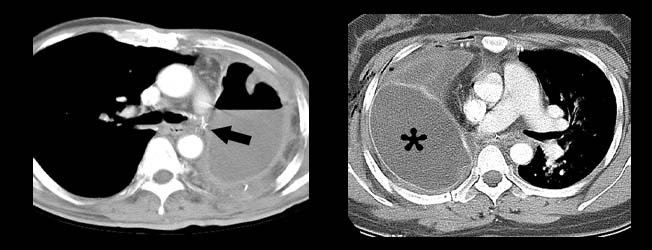

History: a 75 year old man status post partial left upper lobectomy, complicated by pneumothoraces status post chest tube placemente, presented with diffuse crepitus.

A chest radiograph was performed and is shown below. Radiographs: Diffuse subcutaneous emphysema and pneumomediastinum. Patchy basilar opacities In keeping with atelectasis and a probable small amount of left pleural fluid. Small biapical pneumothoraces

Chest CT: Extensive postoperative subcutaneous emphysema and pneumomediastinum. There is a moderate left-sided pneumothorax after left upper partial lobectomy, despite the presence o left chest tube with its lip at the left ape

Diagnosis: latrogenic subcutaneous emphysema